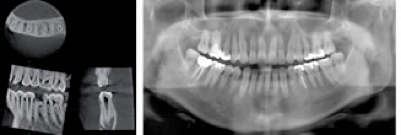

通常のレントゲン写真は一方向からしかX線を当てられないので、得られる情報も平面的な写真でしかありません.

対するCT写真は3次元的な画像を撮れるので、対象物を輪切りにして見たり、様々な方向から立体的に評価する事ができます.これにより、例えば顎の骨の中をどのように神経や血管が走行しているか、骨の厚み、密度、歯の中の神経の形、歯の根っこの先の曲がり具合など、詳細に評価できるので、手術を安全かつ安心して受けて頂く事が可能になります.